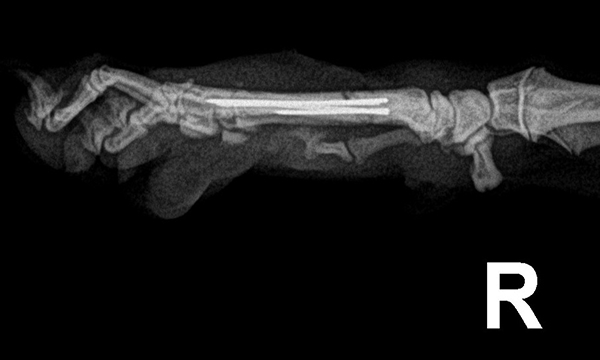

수술케이스 ② 보*강아지 - 요척골 단순골절

수술케이스 2 before BEFORE

수술케이스 2 after AFTER